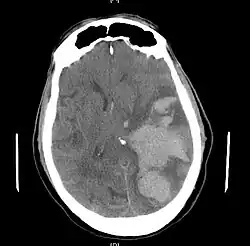

MRI showing injury due to brain herniation